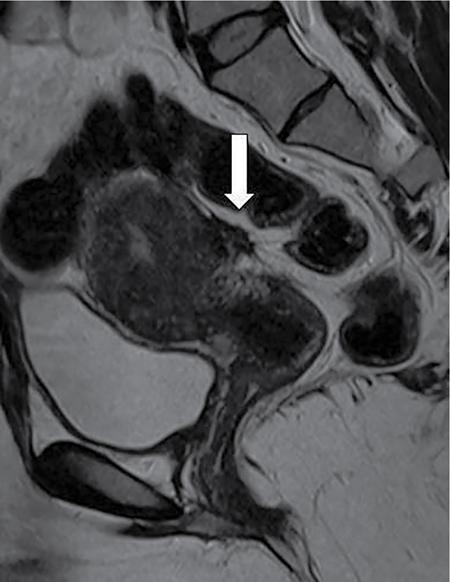

Venkatraman Indiran Bridging vessel sign Multiple vascular channels (white arrows) connecting uterus (black arrow) to an adjacent pelvic mass on imaging studies, is known as the ‘bridging vessel’ or ‘bridging vascular’ sign. Originally described on colour Doppler imaging, but also seen on computed tomography (CT) or magnetic resonance imaging (MRI). Helps in differentiating a mass of uterine origin, typically a subserosal fibroid, from other pelvic masses. Sensitivity and specificity of ‘bridging vessel sign’ in identifying subserosal fibroids range from 90% to 100%. (Best seen when subserosal fibroid is larger than 3 cm in diameter.) Ovarian masses invading the uterus may rarely produce a falsely positive bridging vessel sign. Broccoli sign Submucosal uterine leiomyoma prolapsing into the endocervical canal, along with its stalk in the uterine cavity on sagittal T2-weighted images together is called as ‘broccoli sign’ (white arrow). Submucosal uterine leiomyoma Bunch of grapes Intrauterine mass with cystic spaces without any associated foetal parts on ultrasound (white arrows) classically gives a ‘snow storm’ or ‘bunch of grapes’ appearance. Complete hydatidiform mole Hourglass sign Deep infiltrating endometriosis (DIE) affecting the posterior urinary bladder wall, usually in the midline, causes loss of its distensibility, resulting an hourglass configuration of urinary bladder. Deep infiltrating endometriosis (DIE) Hyperechoic line sign Normal endometrium surrounding the endometrial polyp on ultrasound appear as a hyperechoic rim on transvaginal ultrasound is called as ‘hyperechoic line sign’. Hyperechoic line sign represents a focal intracavitary lesion. Endometrial polyp Indian head dress sign/moose antler sign In deep infiltrating endometriosis (DIE), adhesions between the anterior wall of rectosigmoid and posterior wall of uterus, stretches the muscular layer of the bowel and creates an infiltrative nodule with parallel lines that extend from the adhesion to the rectosigmoid. This is called as ‘Indian head dress sign/moose antler sign’ (white arrow). This is seen on sagittal T2-weighted images as well as transvaginal ultrasound. Deep infiltrating endometriosis (DIE) Interstitial line sign An echogenic line that extends into the upper regions of the uterine horn and borders the margin of the intramural gestational sac is called as the ‘interstitial line sign’ (white arrow). Seen best on transabdominal/transvaginal ultrasound. Specific finding of interstitial pregnancy Mushroom cap sign Mushroom-shaped lesion which is seen displaced into the bowel lumen in patients with solid invasive endometriosis of the rectosigmoid colon on axial or sagittal T2-weighted MRI is called as ‘mushroom cap sign’ (red box and white arrow). Low signal intensity base of the mushroom corresponds to hypertrophy and fibrosis of the muscularis propria, whereas the high intensity cap represents oedematous mucosa and submucosa. Deep infiltrating endometriosis (DIE) Pedicle artery sign Feeding vessel sign Central vessel entering the endometrium from the surrounding myometrium colour Doppler imaging of the endometrium in endometrial polyps is called as pedicle artery sign (white arrow). Endometrial polyps in women with postmenopausal bleeding. (Sensitivity of 76.5%; specificity of 95.3%.) Popcorn ball calcification Dense, amorphous calcifications of uterine fibroids seen on the plain radiographs is called as ‘popcorn calcification’ (white arrow). Confluent, coarse calcification constitutes the most specific radiographic sign of a benign uterine fibroid; but only 10% or fewer of fibroids show calcification. Question mark sign of uterus The uterine corpus that is flexed backward with the fundus of the uterus facing the posterior pelvic compartment and the cervix directed anteriorly toward the urinary bladder, is called as question mark sign of uterus (white arrow). Also called as comma-shaped uterus. 93% specificity and 75% sensitivity in diagnosing adenomyosis uterus. Sliding organs’ sign When the uterus and ovaries glide freely over the posterior and anterior organs (such as rectum and urinary bladder, respectively) during real-time dynamic transvaginal sonography, it is called as ‘positive sliding organs’ sign’. In case of adhesions due to endometriosis, free gliding of organs is absent and is called as negative sliding sign. Snowstorm sign Grainy appearance with low-level homogeneous internal echoes which move slowly downward due to their viscosity seen in endometrioma on transvaginal ultrasound is called as snowstorm sign. Endometriomas Split fibre sign Presence of curvilinear T2 hypointense strands within the degenerated leiomyoma separated by the fluid accumulation and oedema is called as the ‘split fibre’ sign. Split fibre sign on T2-weighted MRI can be used to differentiate hydropic degeneration from other conditions like malignant change. Three-line sign or triple line sign or trilaminar appearance Shortly before ovulation, two additional bright linear echoes outline two hypoechoic layers of endometrium with a central hyperechoic line in the endometrium (white arrow). It is called as the ‘three-line sign’ or ‘triple line sign’ or trilaminar appearance. A triple-line pattern with a moderate endometrial thickness is associated with a good clinical outcome on in-vitro fertilization. Venetian blind shadowing Also known as ‘rain shower’ appearance Heterogeneous myometrial appearance due to hyperechoic heterotopic endometrial tissue and hypoechoic hyperplastic smooth muscle appearing as vertical linear bands of shadows on ultrasound is called as ‘Venetian blind shadowing’. Classically described in uterine adenomyosis; sometimes in uterine fibroids also. Bead on strings sign Thickened endosalpingeal longitudinal folds within a dilated fallopian tube without wall thickening appears as small mural nodules on cross-sectional images on ultrasound is called as ‘bead on strings’ appearance. Seen in chronic salpingitis Beaded tube Multiple constrictions along the course of fallopian tube may form due to scarring is seen in genitourinary tuberculosis and shows a ‘beaded’ appearance. Female genital tuberculosis Cogwheel sign Thickened endosalpingeal longitudinal folds within a dilated fallopian tube with thickened wall appears as small mural nodules on cross-sectional images across the long axis of the fallopian tube on ultrasound (white arrows) produce a characteristic ‘cogwheel’ appearance. Seen in acute salpingitis. The presence of thickened longitudinal folds is pathognomonic for hydrosalpinx. Cobblestone tube Rounded filling defects in cases of fallopian tube tuberculosis are called as the cobblestone pattern. Is an effective radiographic sign of intraluminal scarring and adhesions. Female genital tuberculosis Golf club tube Occlusion of the isthmus or fimbrial end of the fallopian tube and filling up of the tube with serous or clear fluid produces a moderate dilatation at the fimbrial end, produces a ‘golf club–like appearance’. Female genital tuberculosis Halo sign Thin radiolucency seen separating the loculated peritubal collection from the dilated tube, is known as the ‘halo sign’. This radiolucent halo represents the thickened wall of the tube. Female genital tuberculosis Incomplete septation sign Thin linear structures appearing to protrude into the tubular cystic adnexal structures, but not touching the opposite walls is called ‘incomplete septation sign’ of hydrosalpinx. Apparent septae are due to apposition of the inner walls of the dilated and folded fallopian tube. Hydrosalpinx Pipe stem tube Rigid contour of the fallopian tube seen in cases of fallopian tube tuberculosis is called as ‘pipe stem appearance’. Female genital tuberculosis Leash sign Typical eccentric leash of vessels on colour Doppler (white arrow) showing a low resistance placental type of flow on spectral Doppler in fallopian tube ectopic pregnancies is called as leash sign.